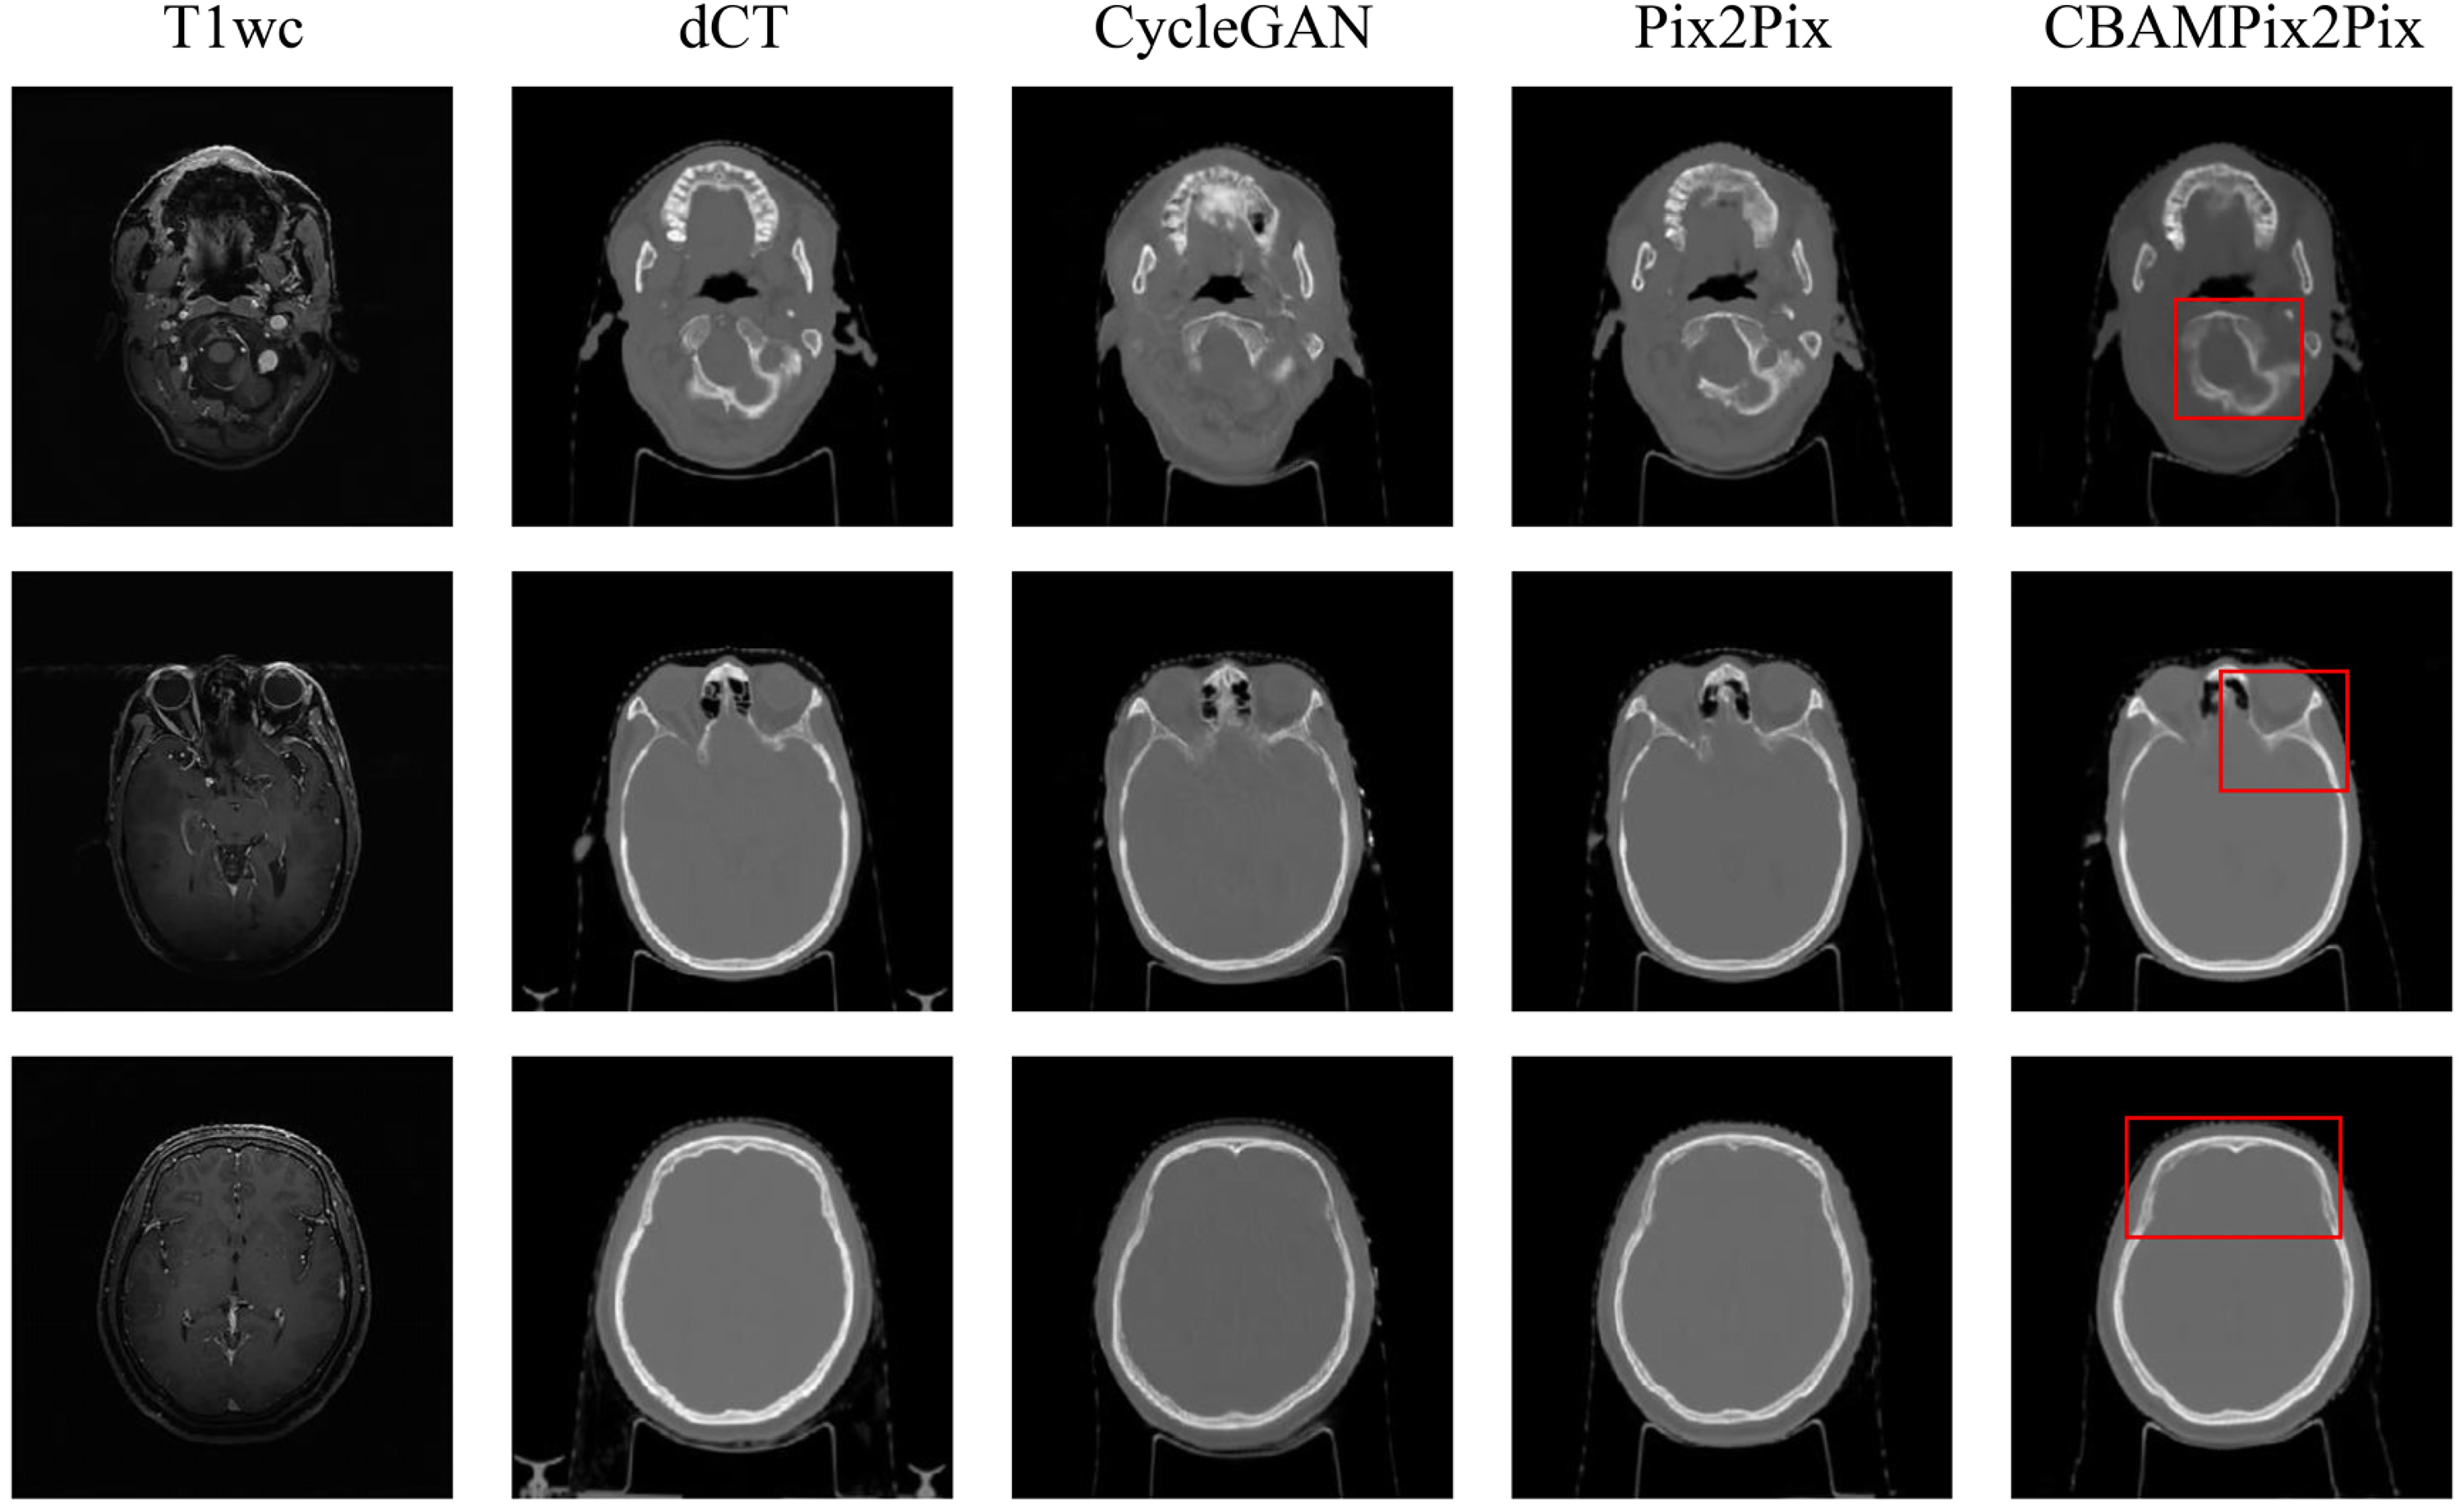

The three models were trained in 36 (CycleGAN), 16 (Pix2Pix), and 17(CBAMPix2Pix) hours, respectively. Once the models have been trained, it took a few seconds to generate sCT images from new MR volume image. Figure 3 shows the visual comparison at different anatomical locations, which contains the axial view of the original MR, the corresponding dCT, and sCT images generated from CycleGAN, the Pix2Pix, the proposed CBAMPix2Pix. In the visual inspection, the generated results of our method are more consistent with the dCT compared with other two methods in terms of global and local imaging regions. As can be seen in Figure 3, the sCT generated using CBAMPix2Pix showed sharper boundaries than the sCT generated using the original CycleGAN and Pix2Pix.

Comparison of deformed CT(dCT) and synthetic CT(sCT) images generated by different models. The first and second columns show MR images and dCT. And the third, fourth columns, and the fifth column respectively display sCT images generated by the CycleGAN model, the Pix2Pix, and CBAMPix2Pix. Red boxes highlight anatomical regions where CBAMPix2Pix shows the most significant improvement.